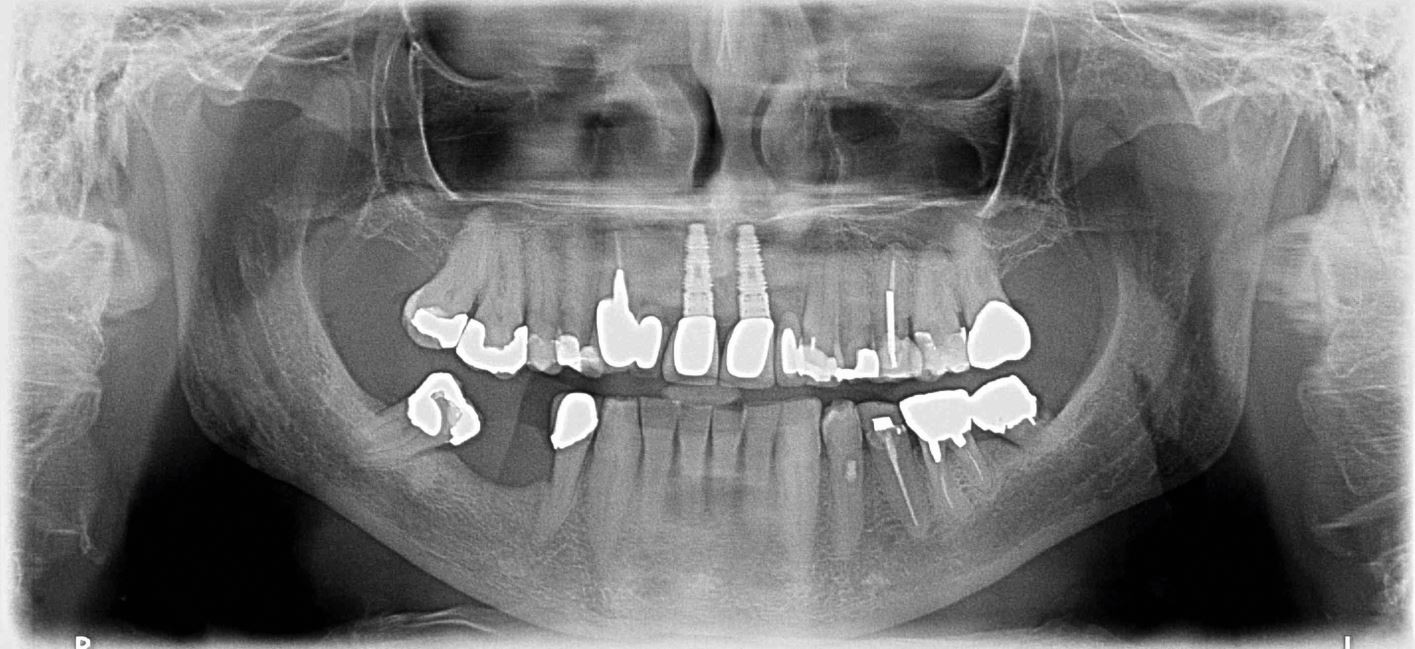

Orthopantomograph of male patient discussed in the text. Of note are the tilted 47 and the cantilever bridge from the root-filled/post-crowned 13 replacing 12